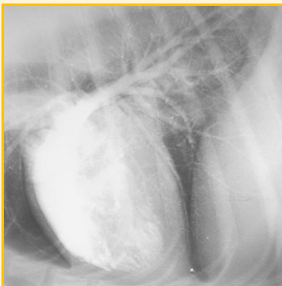

Myelography

Indication to identify spinal lesions that are unable to be identified on a plain radiograph

Myelography involves ..

An injection of a contrast agent into the subarachnoid space to highlight the spinal cord

Myelography may be used to identify compression of the spinal cord, inflammation and CSF obstruction. Also helps to identify whether lesions are extradural, intradural or intramedullary. Potential complications include ..